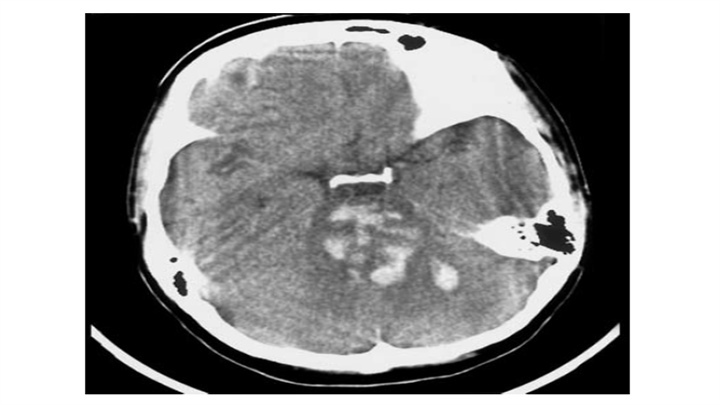

8岁女孩突然昏迷。小脑IPH伴蛛网膜下腔出血,脑干缺血性密度减低,脑积水(侧脑室颞角扩大)。小脑蚓部是“隐性血管瘤”最常见的部位之一。